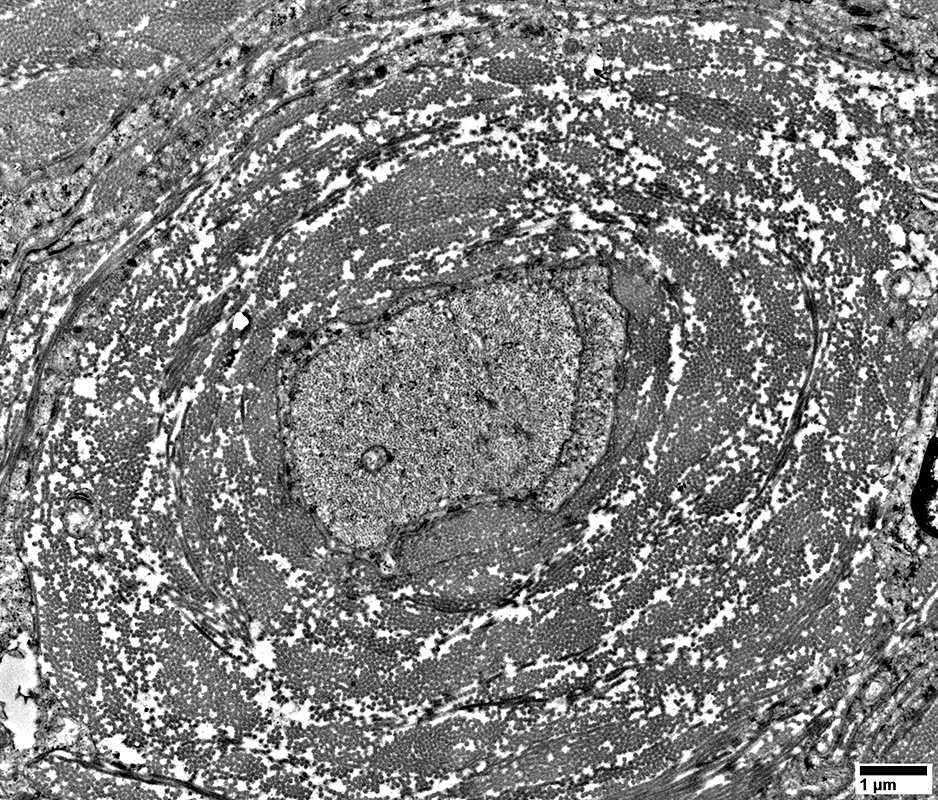

Perineurioma

Layered whorls of cells & processes around, but not immediately neighboring, unmyelinated axon

Central unmyelinated axon: Surrounded by non-myelinating Schwann cell & Collagen

From: R Schmidt

Layered whorls of processes around thinly myelinated axon

Central thinly myelinated axon: Surrounded by Myelin & Collagen

Perineurioma: Layered relationship of neoplasm to other endoneurial cells

Center: Axon, Myelinated or non-myelinated

Around axon: Myelin with Schwann cell, or Schwann cell alone

Surround: Collagen

Periphery: Perineurial cell processes

Interdigitated

Basal lamina: Varied thickness